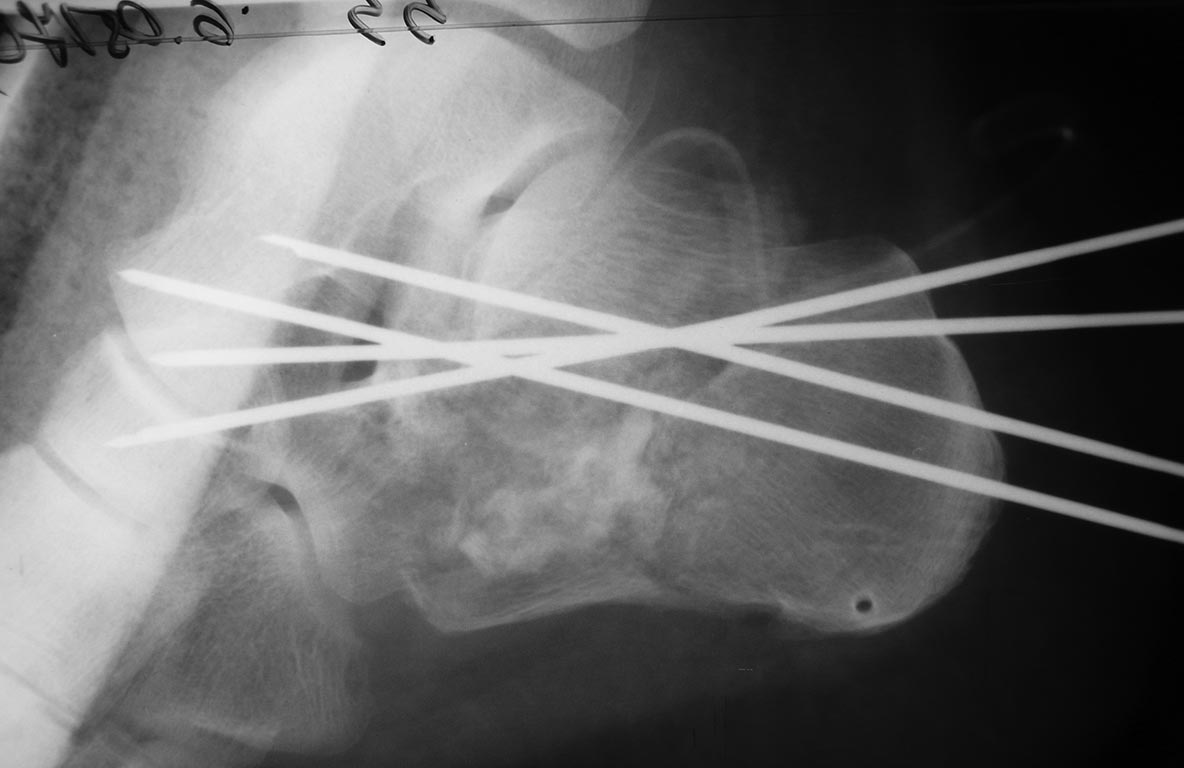

Пациента прооперировал 5 мая. Произвел аутопластику костной крошкой и фиксацию спицами. Выкладываю снимки

Всем привет!Изначально было желание ничего не трогать,заживить,срастить и потом устранить то что беспокоило бы пациента а это вожможно корригирующие остетомии,декомпрессия подлодыжечного пространства и уж совсем край подтаранный дез.Сейчас добра думаю не получилось как заживать будет пластика, пятка укоротилась а это и свод и размер.С уважением!